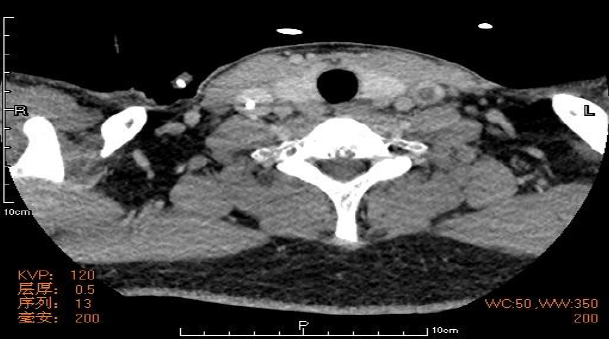

另一篇文献报道一例32岁男性患者,发热、咽痛、关节痛和颈部疼痛及活动受限4天。颈部左侧疼痛肿块,颈部CT提示颈静脉血栓,胸部CT提示肺脓肿,血培养发现不解糖卟啉单胞菌。

图片

图片来源:Intern Med, 2005,44(4):350-353.

该患者的颈部CT提示左颈静脉充盈缺损,长度约为62 mm,考虑血栓形成。